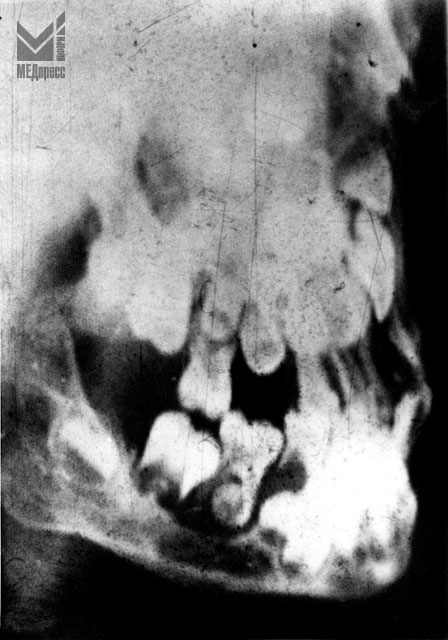

| Рис. 2. Остеолизис в области альвеолярного отростка у второго временного моляра и зачатка постоянного зуба. В области тела челюсти очаг деструкции с четкими контурами. |